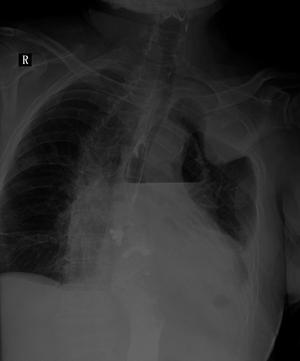

患者、男,66y,食道贲门ca术后13多天,不规则发热,来科照片:

考虑:1、食道胃胸腔吻合术后改变;

2、左侧液气胸;

3、图像欠清,右侧难以观察。

考不考虑左侧下肺背段脓肿?,那个气液平好像在肺内。

另外左侧肺尖区高密度影。是胸膜增厚吗?

1、胸腔胃,术后改变。液平面为胃泡影。

2、左侧胸膜增厚。

1、观察钡剂未流入气液平面内,考虑左后胸腔内包裹性气液平面改变

2、左侧胸壁包裹性胸腔积 液 结合临床病程行ct检查,

这是北京专家的会诊,(二炮总医院远程会诊结论)